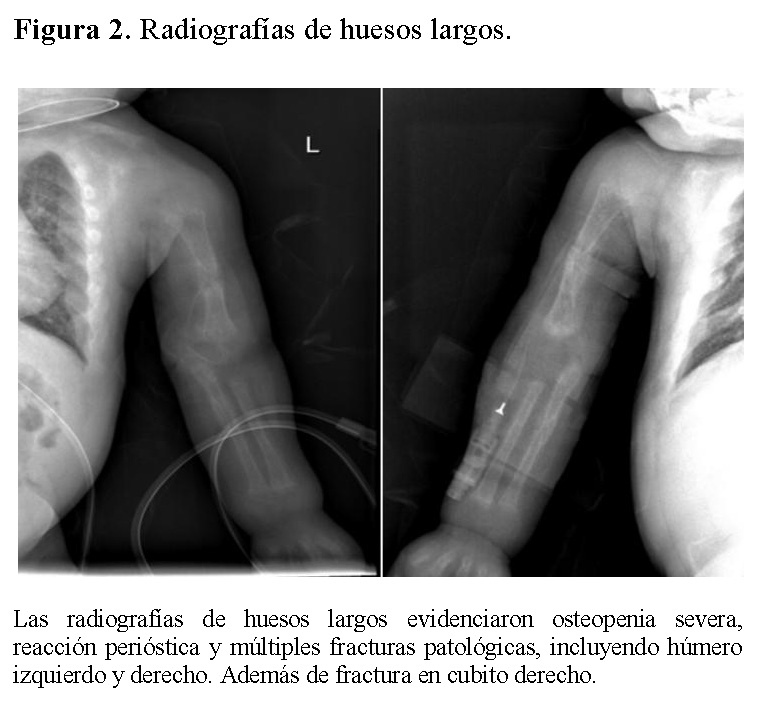

La radiografía de tórax mostró infiltrados parenquimatosos heterogéneos bilaterales, engrosamiento pleural y fracturas costales derechas en fase de consolidación (Figura 1). Las radiografías de huesos largos evidenciaron osteopenia severa, reacción perióstica y múltiples fracturas patológicas, incluyendo húmero derecho e izquierdo, cúbito derecho y fémur derecho (Figuras 2 y 3).